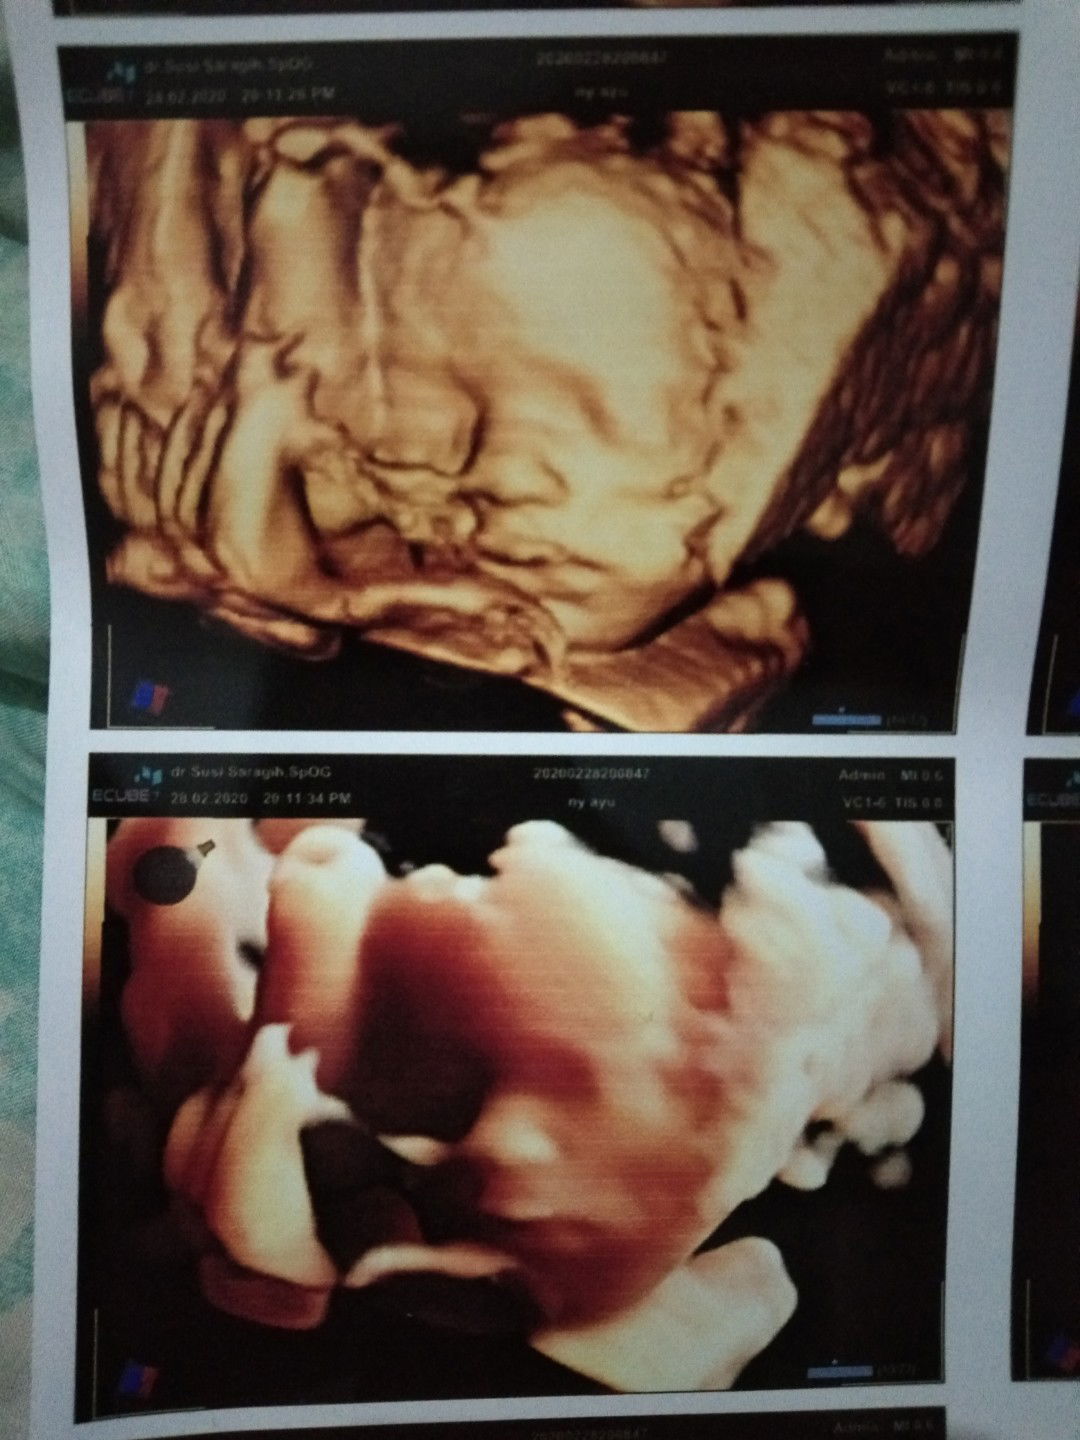

mungkin ngikutin bibir yayahnya ?